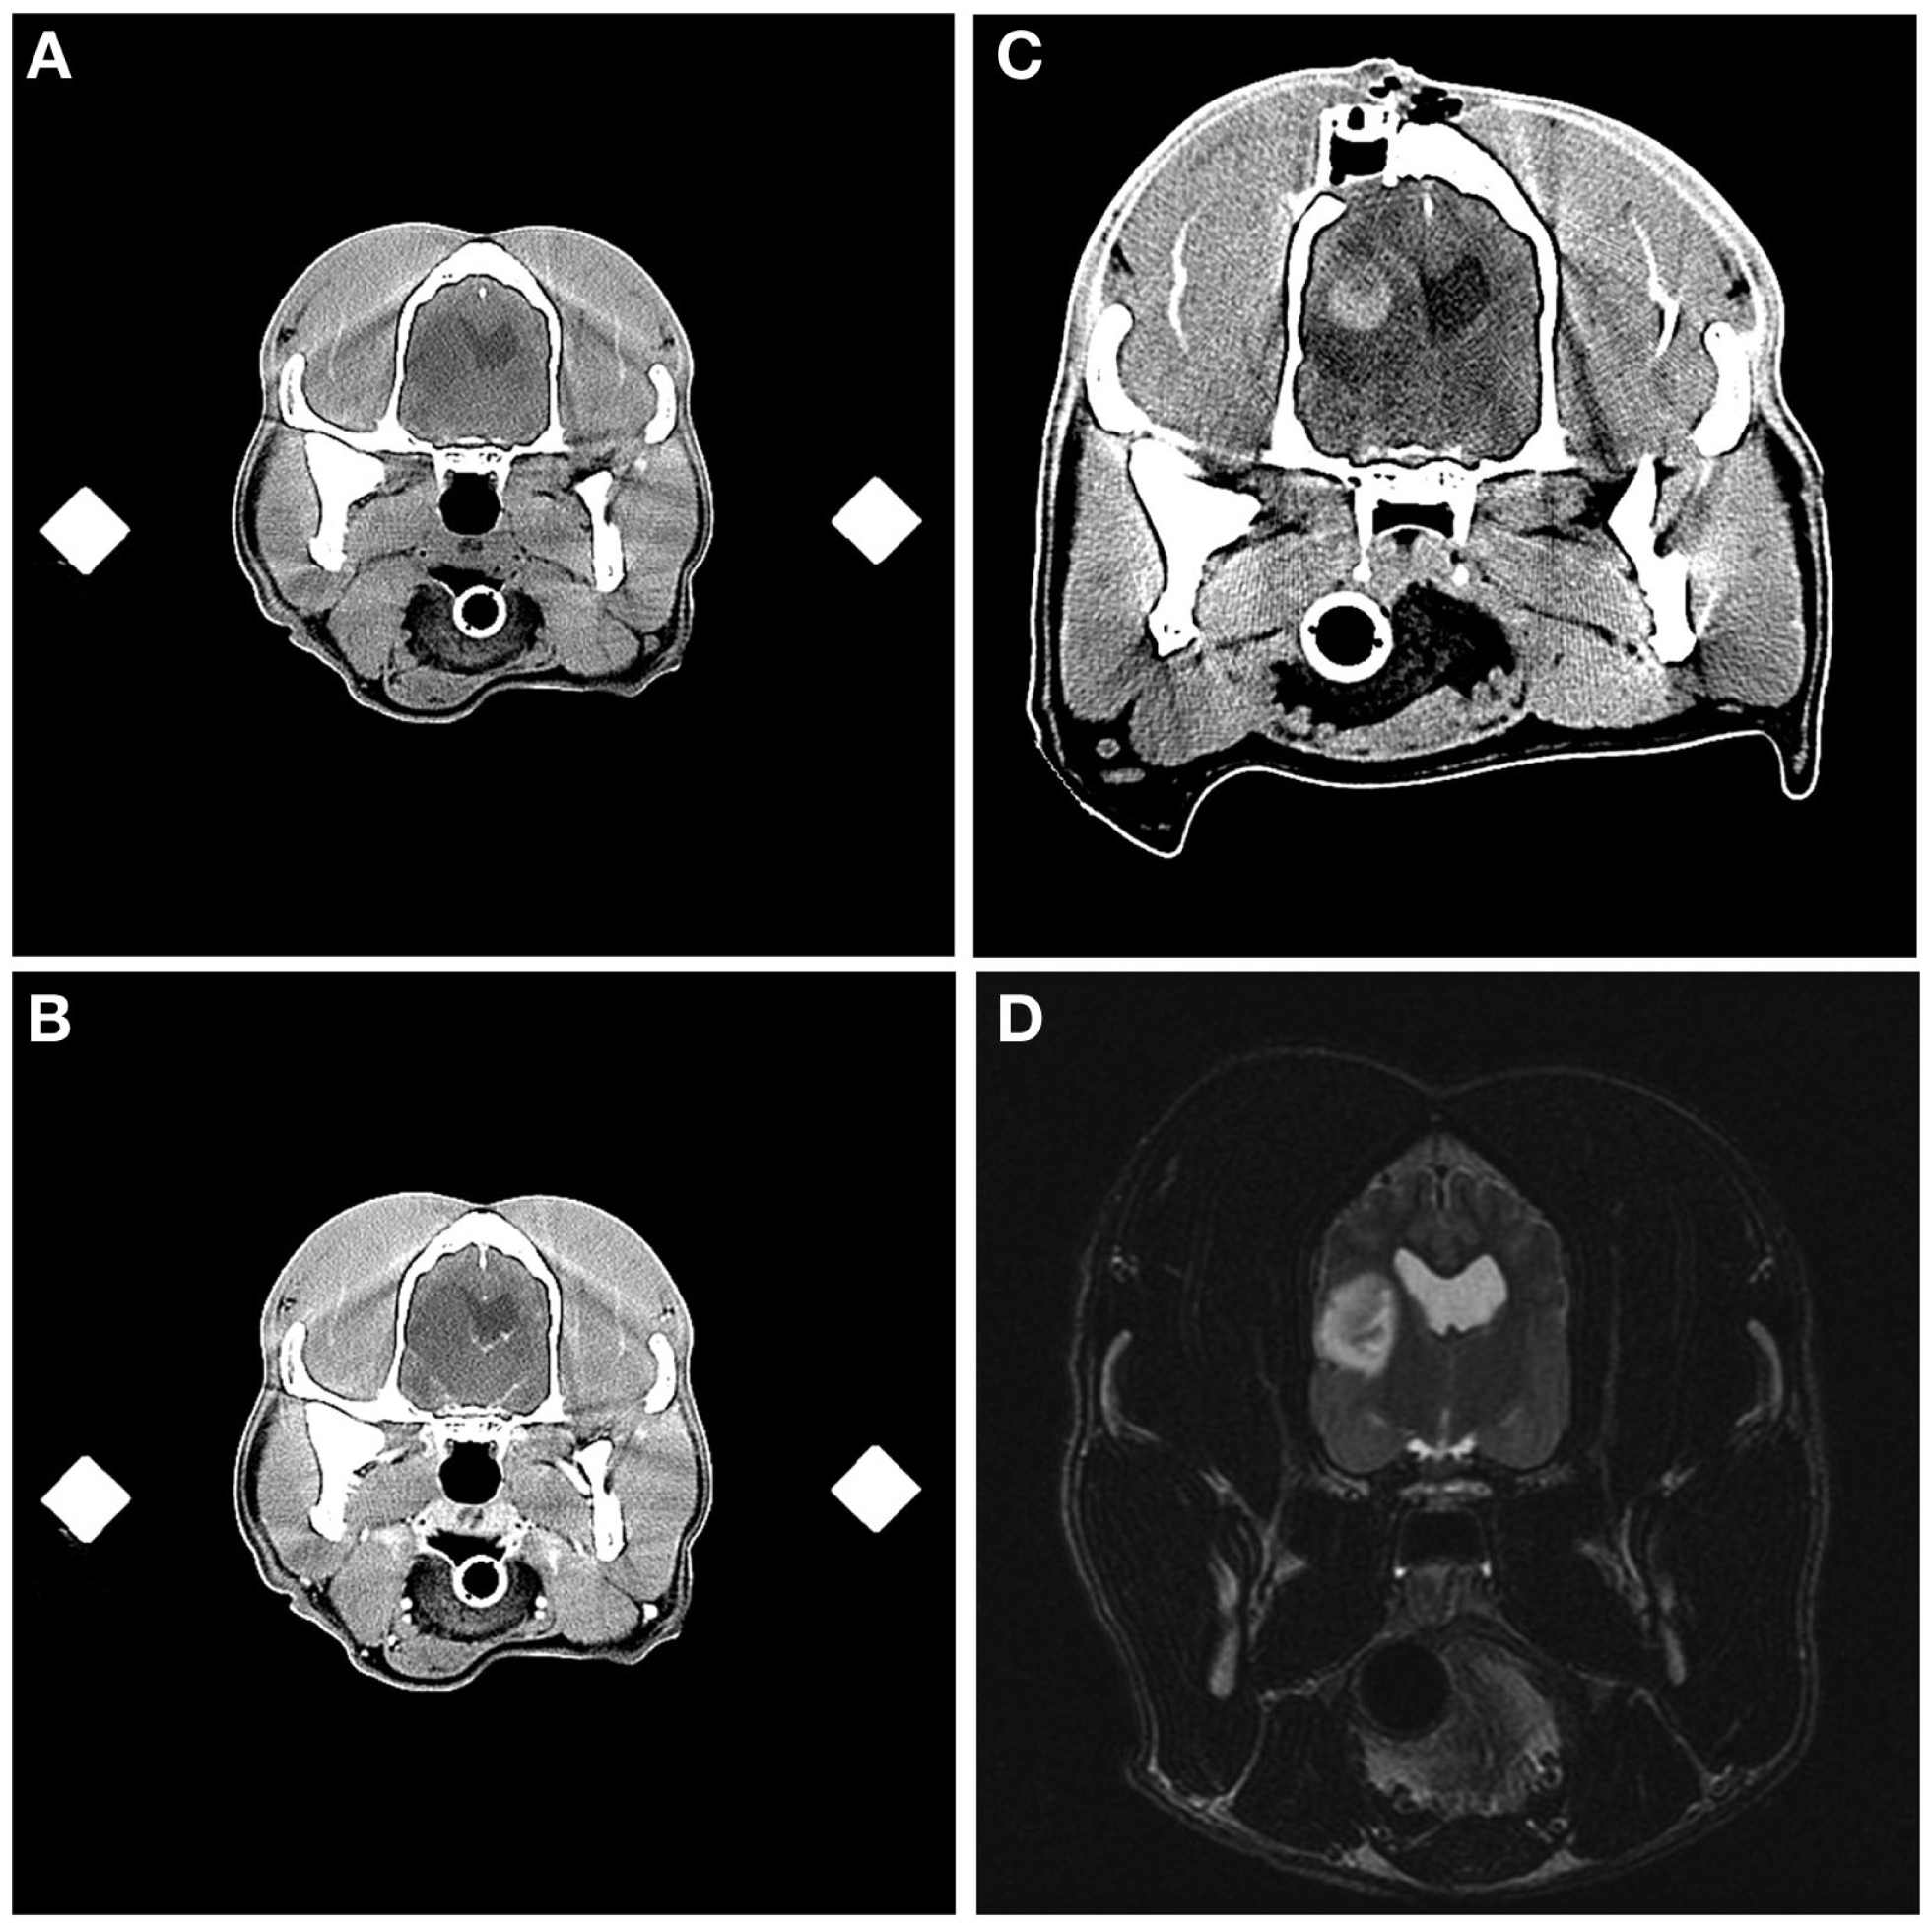

Aside from the changes anticipated from the FBSB procedure, including the presence of craniectomy defects and small amounts of gas or hemorrhage in the soft-tissues overlying the calvarium, abnormalities were observed in immediate post-biopsy CT examinations in 6/26 dogs. These included intracranial or intratumoral hemorrhage (Figure 6) in two dogs, pneumocephalus contained within in the biopsy track in two dogs, ventricular pneumocephalus in the dog in which the lateral ventricle was compromised during the biopsy, and hypoattenuating mass effect in the brain parenchyma surrounding the biopsy track, consistent with edema, in the one dog that experienced transient clinical decline.

Figure 6

Intracranial hemorrhage resulting from frame-based stereotactic biopsy of a Grade III oligodendroglioma. Transverse, pre- (A) and post-contrast (B) stereotactic planning CT scans demonstrating hypoattenuating and non-enhancing mass lesion in the temporal region. On the immediate post-biopsy, pre-contrast CT scan, biopsy-induced intracranial hemorrhage is apparent as an ovoid, hyperattenuating lesion contained within the dorsal and central aspect of the previously described hypoattenuating mass (C). The craniectomy and implanted catheter guide pedestal (C) through which the biopsy was performed are visible in the parietal bone dorsal to the lesion. Initial diagnostic T2-weighted, transverse MR image (D), illustrating the hyperintense lesion in the temporal lobe of this patient.